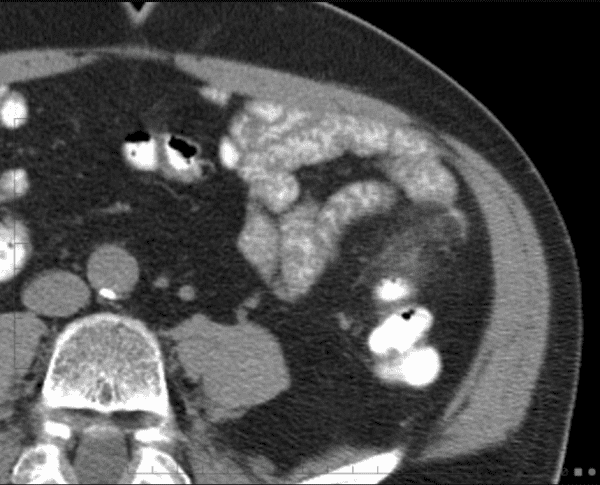

Viêm túi thừa

Viêm túi thừa - Ảnh 3

» Thông tin: Nam giới – 25 tuổi.

» Lâm sàng: Đau hố chậu trái.